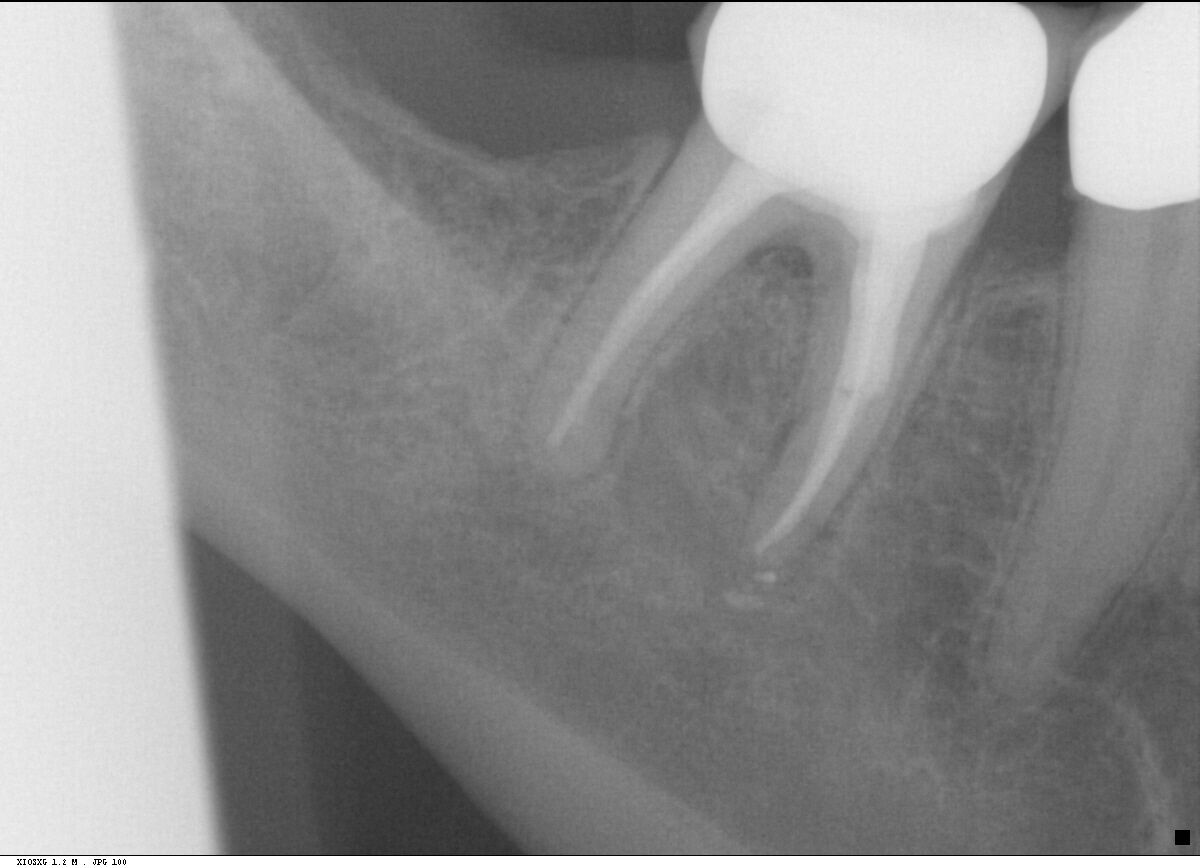

Fall 5: Starke Wurzelkrümmung

Endodontie Fall 5: Starke Wurzelkrümmung

Vor der Behandlung

Kontrolle nach Wurzelfüllung